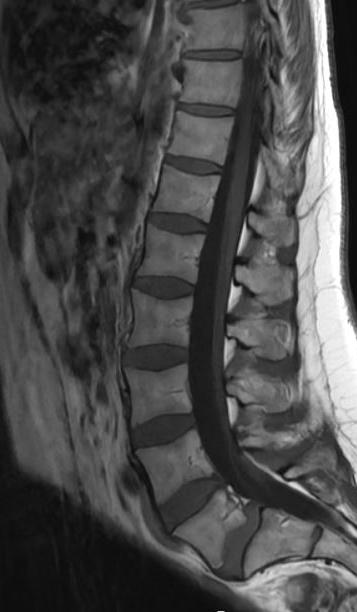

MR ländrygg. Alla medelålders patienter med ont i ländryggen vill ju ha en förklaring och allra helst också fina bilder från en högstatusundersökning som MR. NU! Men har vi råd både ekonomiskt och miljömässigt med den här fortsatta produktionsökningen inom röntgen?

MR utvecklas mot snabbare och mer specifika sekvenser, korta protokoll och mer kvantitativa metoder.3 Nya snabba MR-sekvenser och nya rekonstruktionsalgoritmer kan minska undersökningstiden samtidigt som hög bildkvalitet bibehålls. Moderna 3eller 7-Tesla MR-kameror har potentialen att maximera bildkvaliteten som är viktigt för att kunna visualisera små strukturer som handledens ligament och dess skador4,5 jämfört med 1,5 T. Tredimensionell MR med planar reformation kan erbjuda möjligheten till rekonstruktion i alla plan som kan vara viktig för mer komplicerade leder som thandled5 eller fotled.6

Dynamisk MR möjliggör bedömning av ledens funktion in vivo under rörelse. Genom denna avbildning kan stabiliteten hos strukturer såsom menisker, brosk, senor och ligament bedömas.19 Dessa sekvenser, som visas som filmer, ger en värdefull insikt i ledens dynamiska aspekter, vilket inte är möjligt med rutinmässigt använda sekvenser. Med denna metod kan man bedöma hur fettvävnaden i knäet påverkas, hur korsbandsgraft fungerar efter operation och även noggrant bedöma meniskerna och meniskstabilitet. Genom denna metod kan skador på meniskers bakre rötter, som är mycket svåra att identifiera med konventionella sekvenser, upptäckas. På så sätt kan antalet förbisedda skador på rötterna minskas.20 Att upptäcka sådana skador är avgörande för att förhindra utvecklingen av degenerativa förändringar.